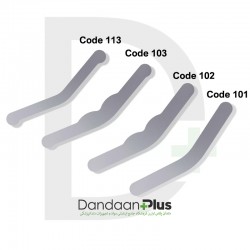

کیت سکشنال ماتریس - Cotisen - Sectional Contoured Matrices Kit

- ضخامت سکشنال ۰.۰۲۵mm

- عرضه کیت با سکشنال ماتریس تیتانیومی (کد کالایی ۱۱۰۲)